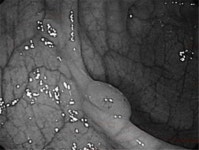

• 대장 | 녹십자 아이메드 강남 건강검진 위/대장 내시경 후기

으로 건강검진을 받고 왔습니다 위, 대장 내시경 포함해서 받고 왔는데 저번엔 다른 병원 건강검진받았었는데 여기도 괜찮더라고요 ​ 대장 내시경 준비~건강검진 후기 시작해 볼게요! ​ 대장 내시경 준비 검진 12시간 전~ Previous image Next image 대장 내시경을 받으시는 분들은 1주일 전 택배가 옵니다 ​ 저는 오전 7시...

• 대장 | 부천 위대장내시경 후기 대장내시경식사까지

부천 건강검진 위대장내시경 후기 장좋은내과 건강검진 받는김에 ​ 별도로 검사 비용 지불하고 위랑 대장 내시경검사도 함께 받았습니다 (위대장내시경 비용 궁금하신 분들은 댓글)​ ​ 병원은 부천 상동 세이브존 6층에 위치한 장좋은내과로 방문했습니다 ​ 긍정적인 후기가 많았고 통화로 이것저것 여쭤봤을 때 다른 병원들...

• 대장 | 이샘병원 수면내시경 및 종합 건강 검진 후기 대장내시경 식사 식단 꿀팁

반갑더라구요😄😄 하지만.. 둘 다 물을 못 마시고 배가 고파서 힘이 없었어요! 빨리 끝나고 물 마시고 싶다는 생각밖에 없었습니다ㅎ ​ ​ 그리고 대망의 수면 위, 대장 내시경을 위해 바늘을 꽂는데 살짝 따끔했어요.. 덩치는 산 만하지만 바늘을 싫어합니다..ㅎ 맨날 와이프가 놀려요 수면 내시경 후기​ 이동형 침대에 옆...